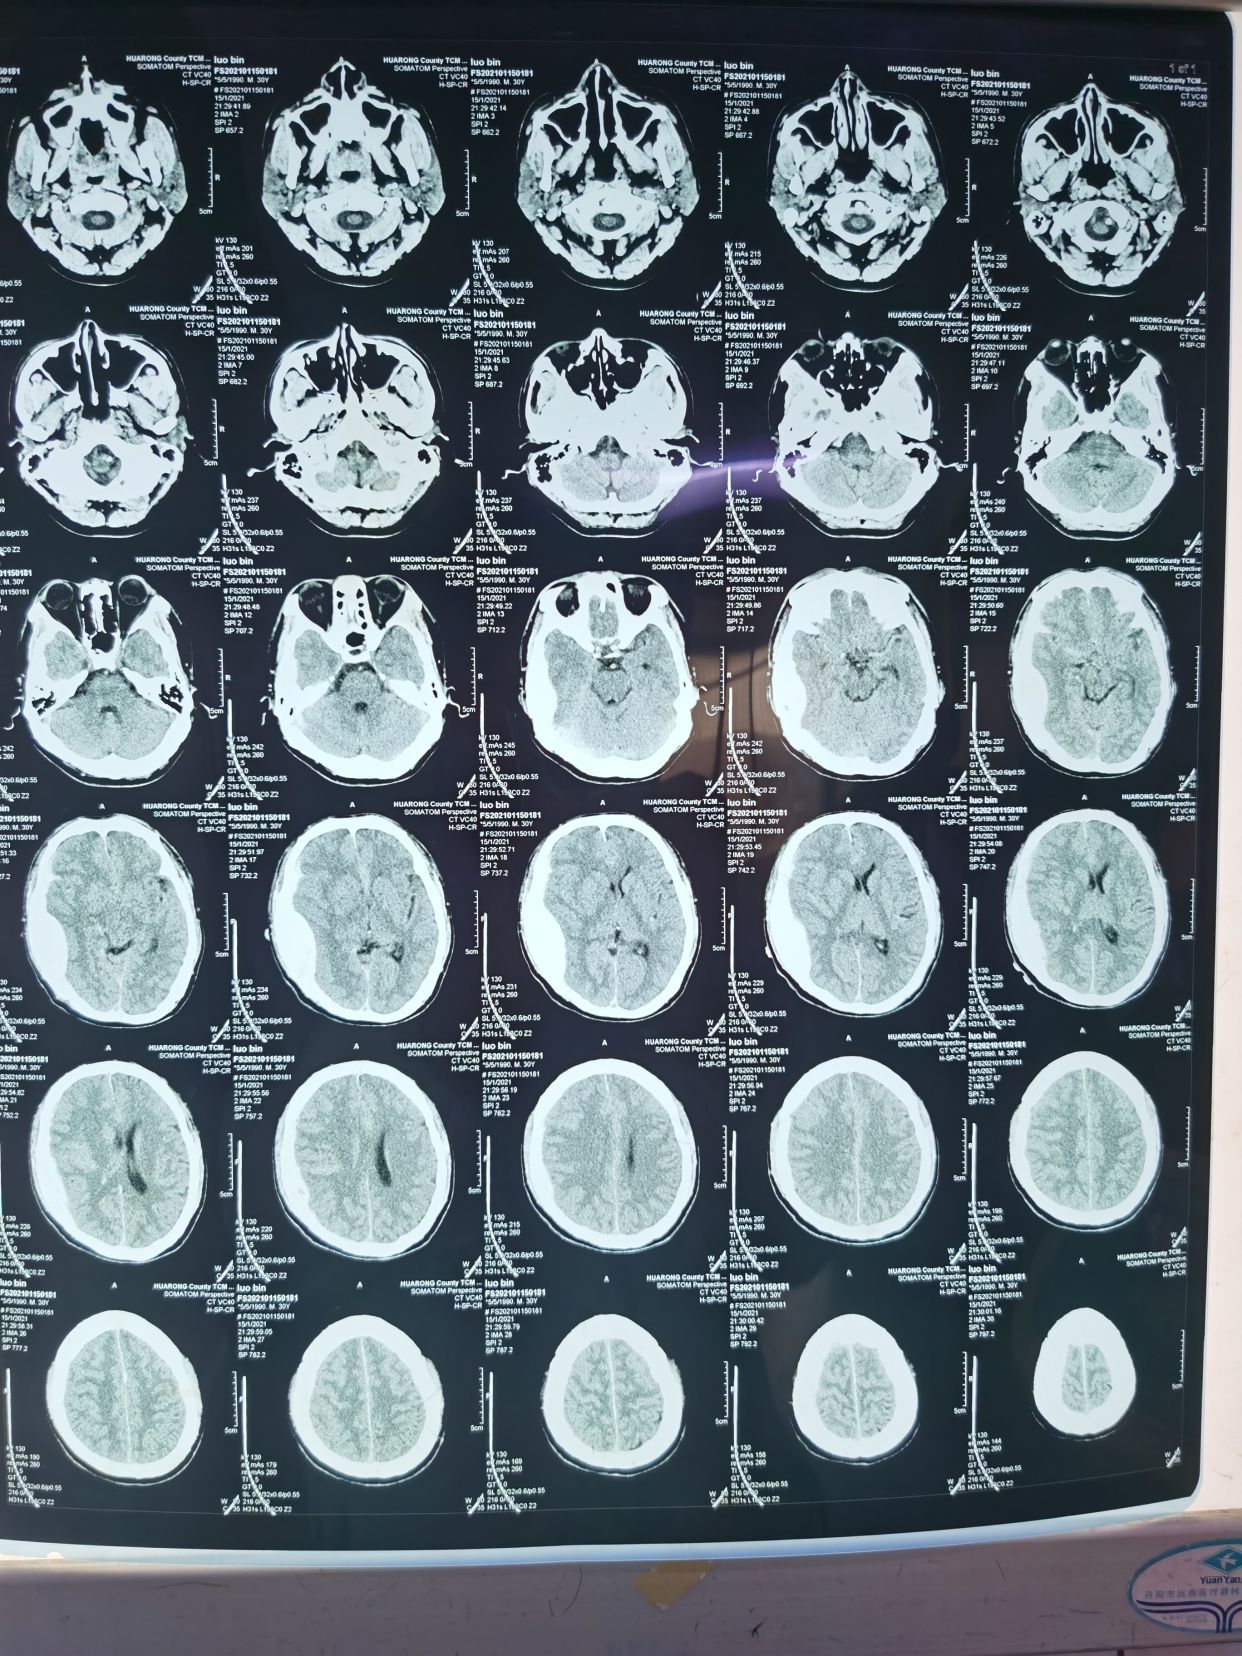

患者31岁,男性。尿毒症,维持性透析,肾性高血压患者。因头痛,恶心,呕吐两天于21年1月15日入院。入院时神志稍模糊,GCS评分=14分。

入院时完善头部CT如下:提示硬膜外血肿并脑疝,硬膜下少量出血。

术后复查CT如下,进一步确认了此为硬膜下血肿,不是硬膜外血肿!

1月19号复查CT,硬膜下血肿显著减少!